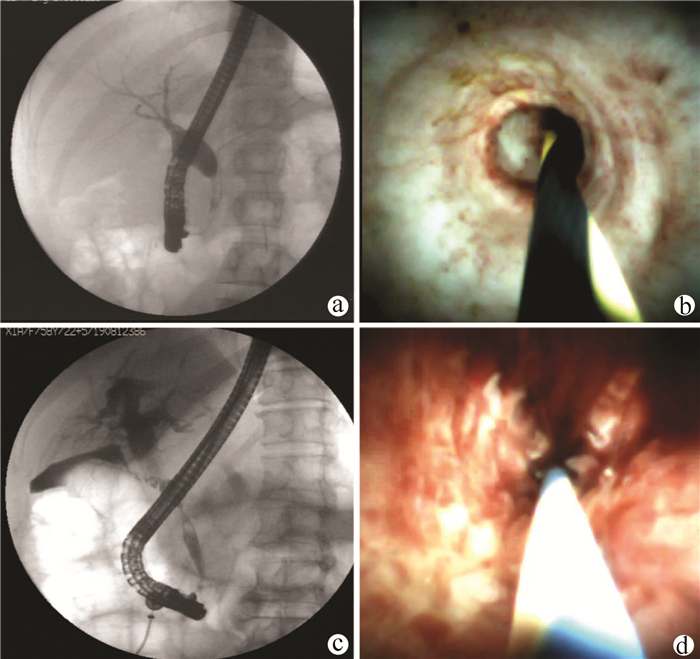

Value of SpyGlass single-operator choledochoscopy system in the diagnosis and treatment of patients with biliary tract diseases

Si ZHAO, Xueru WU, Linlin YIN, Lin MIAO, Guozhong JI, Xiuhua ZHANG

2021, 37(10): 2395-2399. DOI: 10.3969/j.issn.1001-5256.2021.10.027

Abstract(2421) HTML (611) PDF (2327KB)(107)

Abstract:

Objective  To investigate the value of SpyGlass single-operator choledochoscopy system in the diagnosis and treatment of patients with unexplained biliary stricture, complex bile duct stones, or other biliary tract diseases.  Methods  A retrospective analysis was performed for the clinical data of the patients with biliary tract diseases who were diagnosed and treated with SpyGlass in The Second Affiliated Hospital of Nanjing Medical University from December 2017 to June 2020. For the patients with biliary stricture, the biliary lesions were fully visualized under the guidance of SpyGlass, and SpyBite biopsy was performed if necessary; the patients with bile duct stones were treated with SpyGlass-guided direct-view laser lithotripsy; for the patients with gallbladder disease, the cystic duct was superselected with the assistance of SpyGlass. The SpyGlass system was analyzed in terms of its sensitivity, specificity, and accuracy rate in diagnosis and treatment, lithotripsy success rate, stone clearance rate, procedure success rate, and incidence rate of complications.  Results  A total of 58 patients underwent SpyGlass procedure. SpyGlass was used to evaluate biliary stricture of unknown nature in 44 (76%) patients; SpyGlass visual impression had a diagnostic sensitivity of 92% (24/26), a specificity of 94% (17/18), and an accuracy of 93% (41/44), and SpyBite biopsy had a diagnostic sensitivity of 71% (15/21), a specificity of 92% (11/12), and an accuracy of 79% (26/33). SpyGlass was used for the treatment of bile duct stones in 8 patients (14%), with a lithotripsy success rate of 83% (5/6) and a stone clearance rate of 88% (7/8). A guide wire under the SpyGlass system was to superselect the cystic duct in 5 patients (9%), with a procedure success rate of 80% (4/5). In one patient (1%), SpyGlass was used to assist the removal of common bile duct stones after liver transplantation and the treatment of bile duct anastomotic stricture. A total of 5 patients (9%) experienced complications after surgery.  Conclusion  The SpyGlass choledochoscopy system is accurate, safe, and effective in the diagnosis and treatment of unexplained biliary stricture, complex bile duct stones, and other biliary tract diseases.